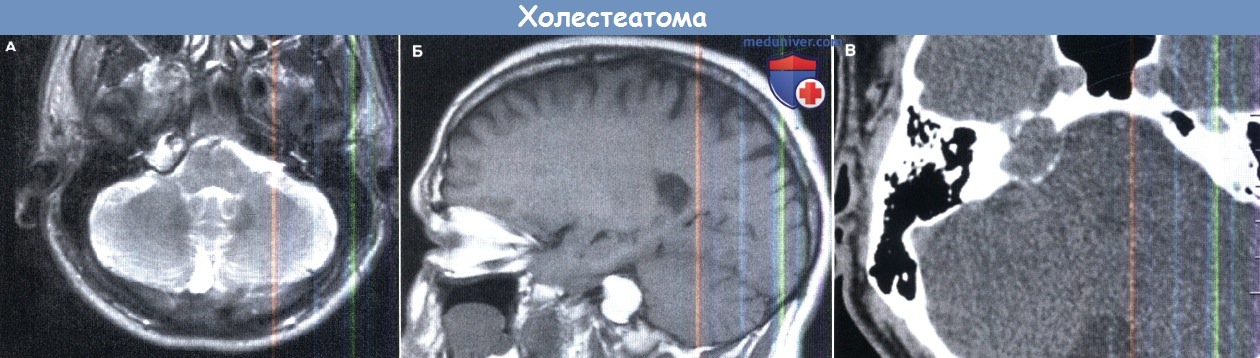

КТ анатомия сосцевидного отростка: особенности и показания